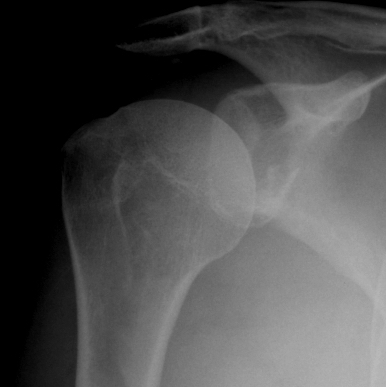

Xray

True AP

Scapular Lateral

Axillary Lateral

Garth (aim beam caudally)

Bony bankart / glenoid rim fractures